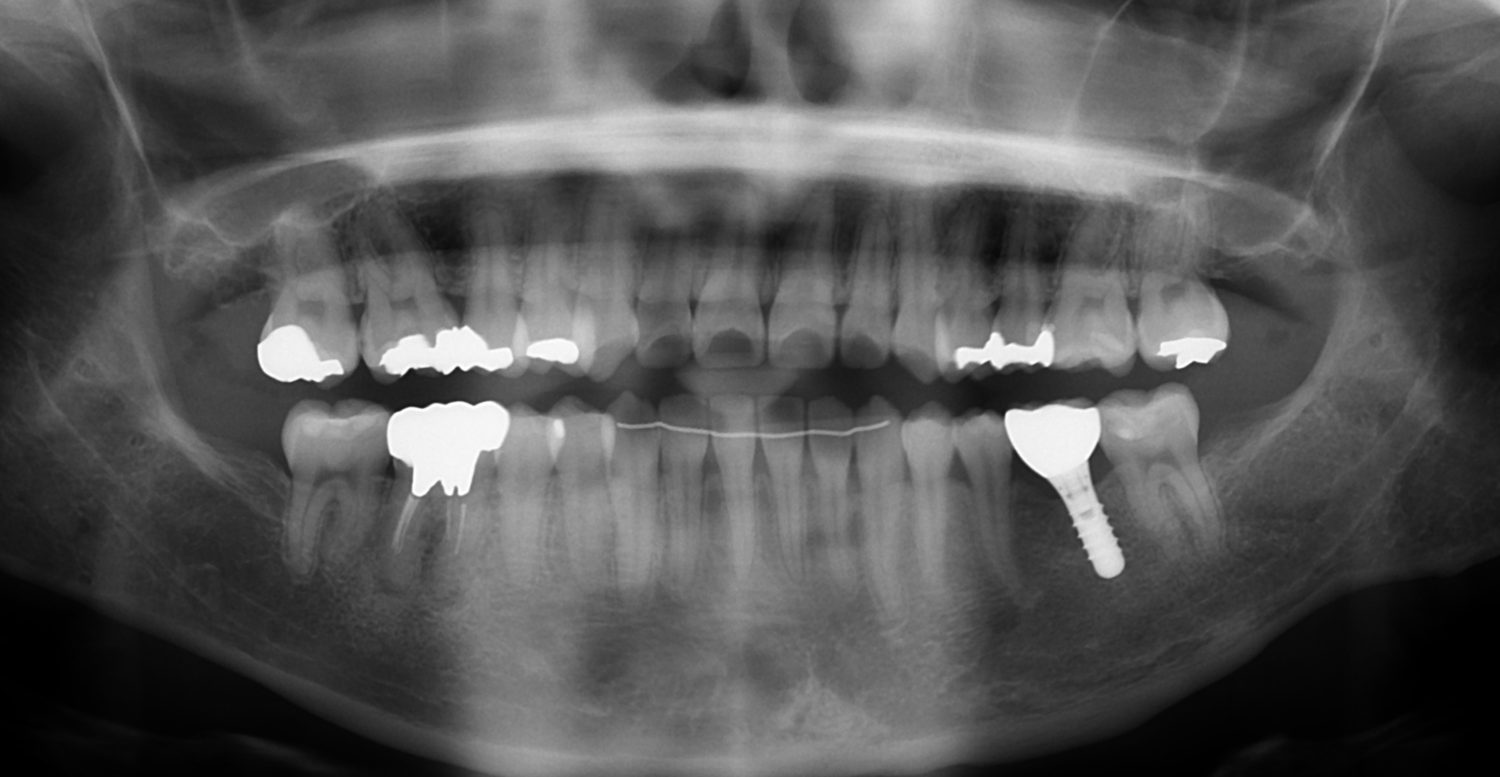

| 主訴 | 30代女性 顎関節が痛い。見た目も気になる |

| 治療内容 | 矯正治療を行いました。 |

| 治療費 | 1,700,000円(税込み) |

| 治療期間 | 3年(矯正治療期間 2年半) |

| 治療回数 | 40回 |

| 想定されたリスク | 術前に精密な診査診断とシミュレーションを行い、インプラントを適正なポジションに埋入しておかないと、インプラント自体が矯正治療の邪魔になるリスクがあった。 |